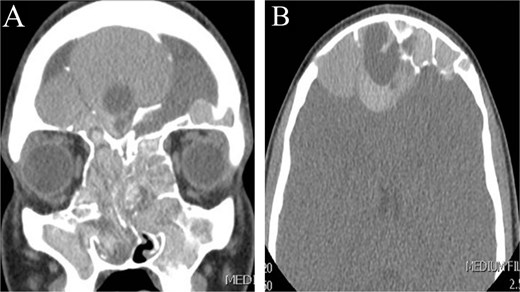

This is a 15-year-old male with no significant medical or surgical history who presented to our otolaryngology clinic with nasal discharge, mild headaches, and nasal itchiness. Preoperative CT scan of the paranasal sinus showed extensive disease with enlargement of the sinuses, predominantly on the right side (Fig. 3). MRI of the brain and paranasal sinus revealed similar findings, with right frontal sinus enlargement and intracranial extension, but intact dura.

CT scan of paranasal sinuses in (A) coronal and (B) axial views, showing extensive disease with enlargement of sinuses, with more expansion of the right frontal sinus.

The patient underwent image-guided ESS. Thick allergic mucin was aspirated and removed from the sinuses, including near the pulsating dura, with no cerebrospinal fluid leak observed during the surgery. Postoperatively, he received a short course of systemic corticosteroids (oral prednisone taper over 3 weeks), intranasal steroids, and a 7-day course of antibiotics to prevent secondary infection. At three-year follow-up, CT scans confirmed no recurrence.